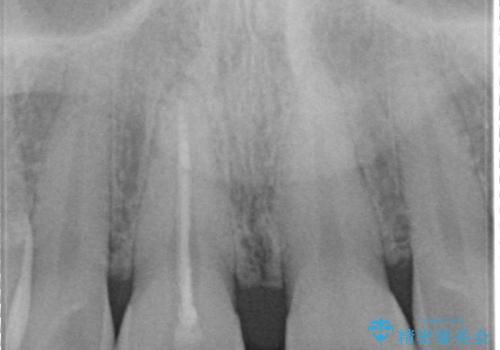

上顎前歯は根管治療後にオールセラミッククラウン(エクセレント)で修復を行なっております。

- 空隙歯列と前歯の変色を主訴に来院されました。

空隙歯列を矯正にて改善した後に歯冠修復を行なっております。